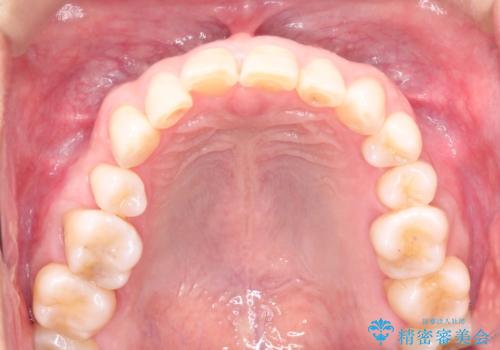

上の前歯の隙間とがたつきをインビザラインできれいな歯並びへ

- 以前矯正治療を他院にて行っており、最近上顎の隙間とガタガタが気になるとのことで来院されました。

上顎のみインビザラインにて矯正治療を行うこととなりました。

使用時間を守っていただけたので、比較的スムーズに矯正を終了することができました。